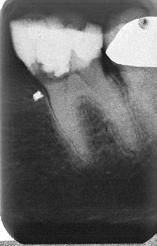

Fig. 2. Tidligere behandlet tand med insufficient eller helt manglende rodfyldning i kanalerne. A. Præmolarer i overkæben med tre insufficiente rodfyldninger og efterfølgende restaurering med stiftopbygning og krone. Desuden første molar uden synlig rodfyldning, men med restaurering, der inddrager pulpakammeret. B. Første molar i overkæben, som kun har synlig rodfyldning i den palatinale kanal. C. Insufficient rodfyldning eller overset rodkanal i første molar i overkæben.

Fig. 2. Previously treated tooth with no or inadequate root filling in canals. A. Maxillary premolars with 3 roots inadequately filled and restored with post and crown. Maxillary first molar with no visible root filling with restoration in pulp chamber and coronal restoration. B. Maxillary first molar with visible root filling only in the palatal canal. C. Inadequate root filling or missed root canal in maxillary first molar.

peroperative faktorer. En af dem er manglende behandling af en rodkanal, enten fordi den ikke blev fundet, eller fordi tandlægen ikke ledte efter den (Fig. 2A-C) (8,9). Det er påvist, at apikal parodontitis forekommer hyppigere i tænder med mindst én ubehandlet eller overset rodkanal (10). Accidentelle perforationer fører ofte til ekstraktion af tanden, men kan almindeligvis undgås med fornuftige endodontiske arbejdsgange (11). Ufuldstændig instrumentering eller forsegling af rodkanalen enten som følge af forkert rodmål eller på grund af fx instrumentfraktur, hyldedannelse eller overinstrumentering af den apikale konstriktion kan føre til, at infektionen persisterer. Rodfile kan frakturere som følge af cyklisk træthedsbrud eller vridningsbelastningsbrud, og incidensraten for brud ligger på 1 % (12). Det sted i tandsættet, der oftest giver anledning til instrumentfraktur, er den apikale del af en mesiofacial rodkanal i en molar (Fig. 3). Kraftig afbøjning af kanalen forøger risikoen for, at filen frakturerer (13). En for kort rodfyldning (> 2 mm fra radiologisk apex) har ligesom overfyldning med guttaperka en nedsat succesrate (14).